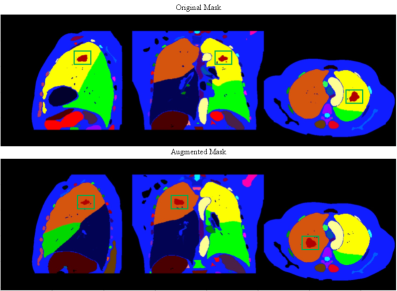

Downstream tumor segmentation. The implementation of all tumor segmentation models is based on the Auto3DSeg444https://monai.io/apps/auto3dseg pipeline. Auto3DSeg is an auto-configuration pipeline designed for 3D medical image segmentation, utilizing MONAI [cardoso2022monai]. The pipeline begins with data analysis to extract global information from the dataset, followed by algorithm generation based on data statistics and predefined templates. It then proceeds to model training to obtain optimal checkpoints. All used tumor dataset is split into 80% for training and 20% for testing. The training set is further divided into five folds for 5-fold cross-validation. We report the segmentation performance on the holdout testing set. For the MAISI CT Generation task, we generate synthetic data from augmented real masks containing tumors. Fig. S2 shows an example of mask augmentation for a case with the lung tumor. For the MAISI Inpainting task, we follow the same setting in DiffTumor [chen2024towards] and use the provided healthy cases in the open-source repository555https://github.com/MrGiovanni/DiffTumor to generate synthetic data with tumors. For both tasks, the amount of synthesized data is equivalent to the original dataset size for each tumor type. We explore the impact of using different amounts of synthetic data for data augmentation in Supplementary Sec. C.

Refer to caption

Figure S2: The example lung tumor mask and corresponding augmented mask. The green boxes highlight the tumor regions in different views.